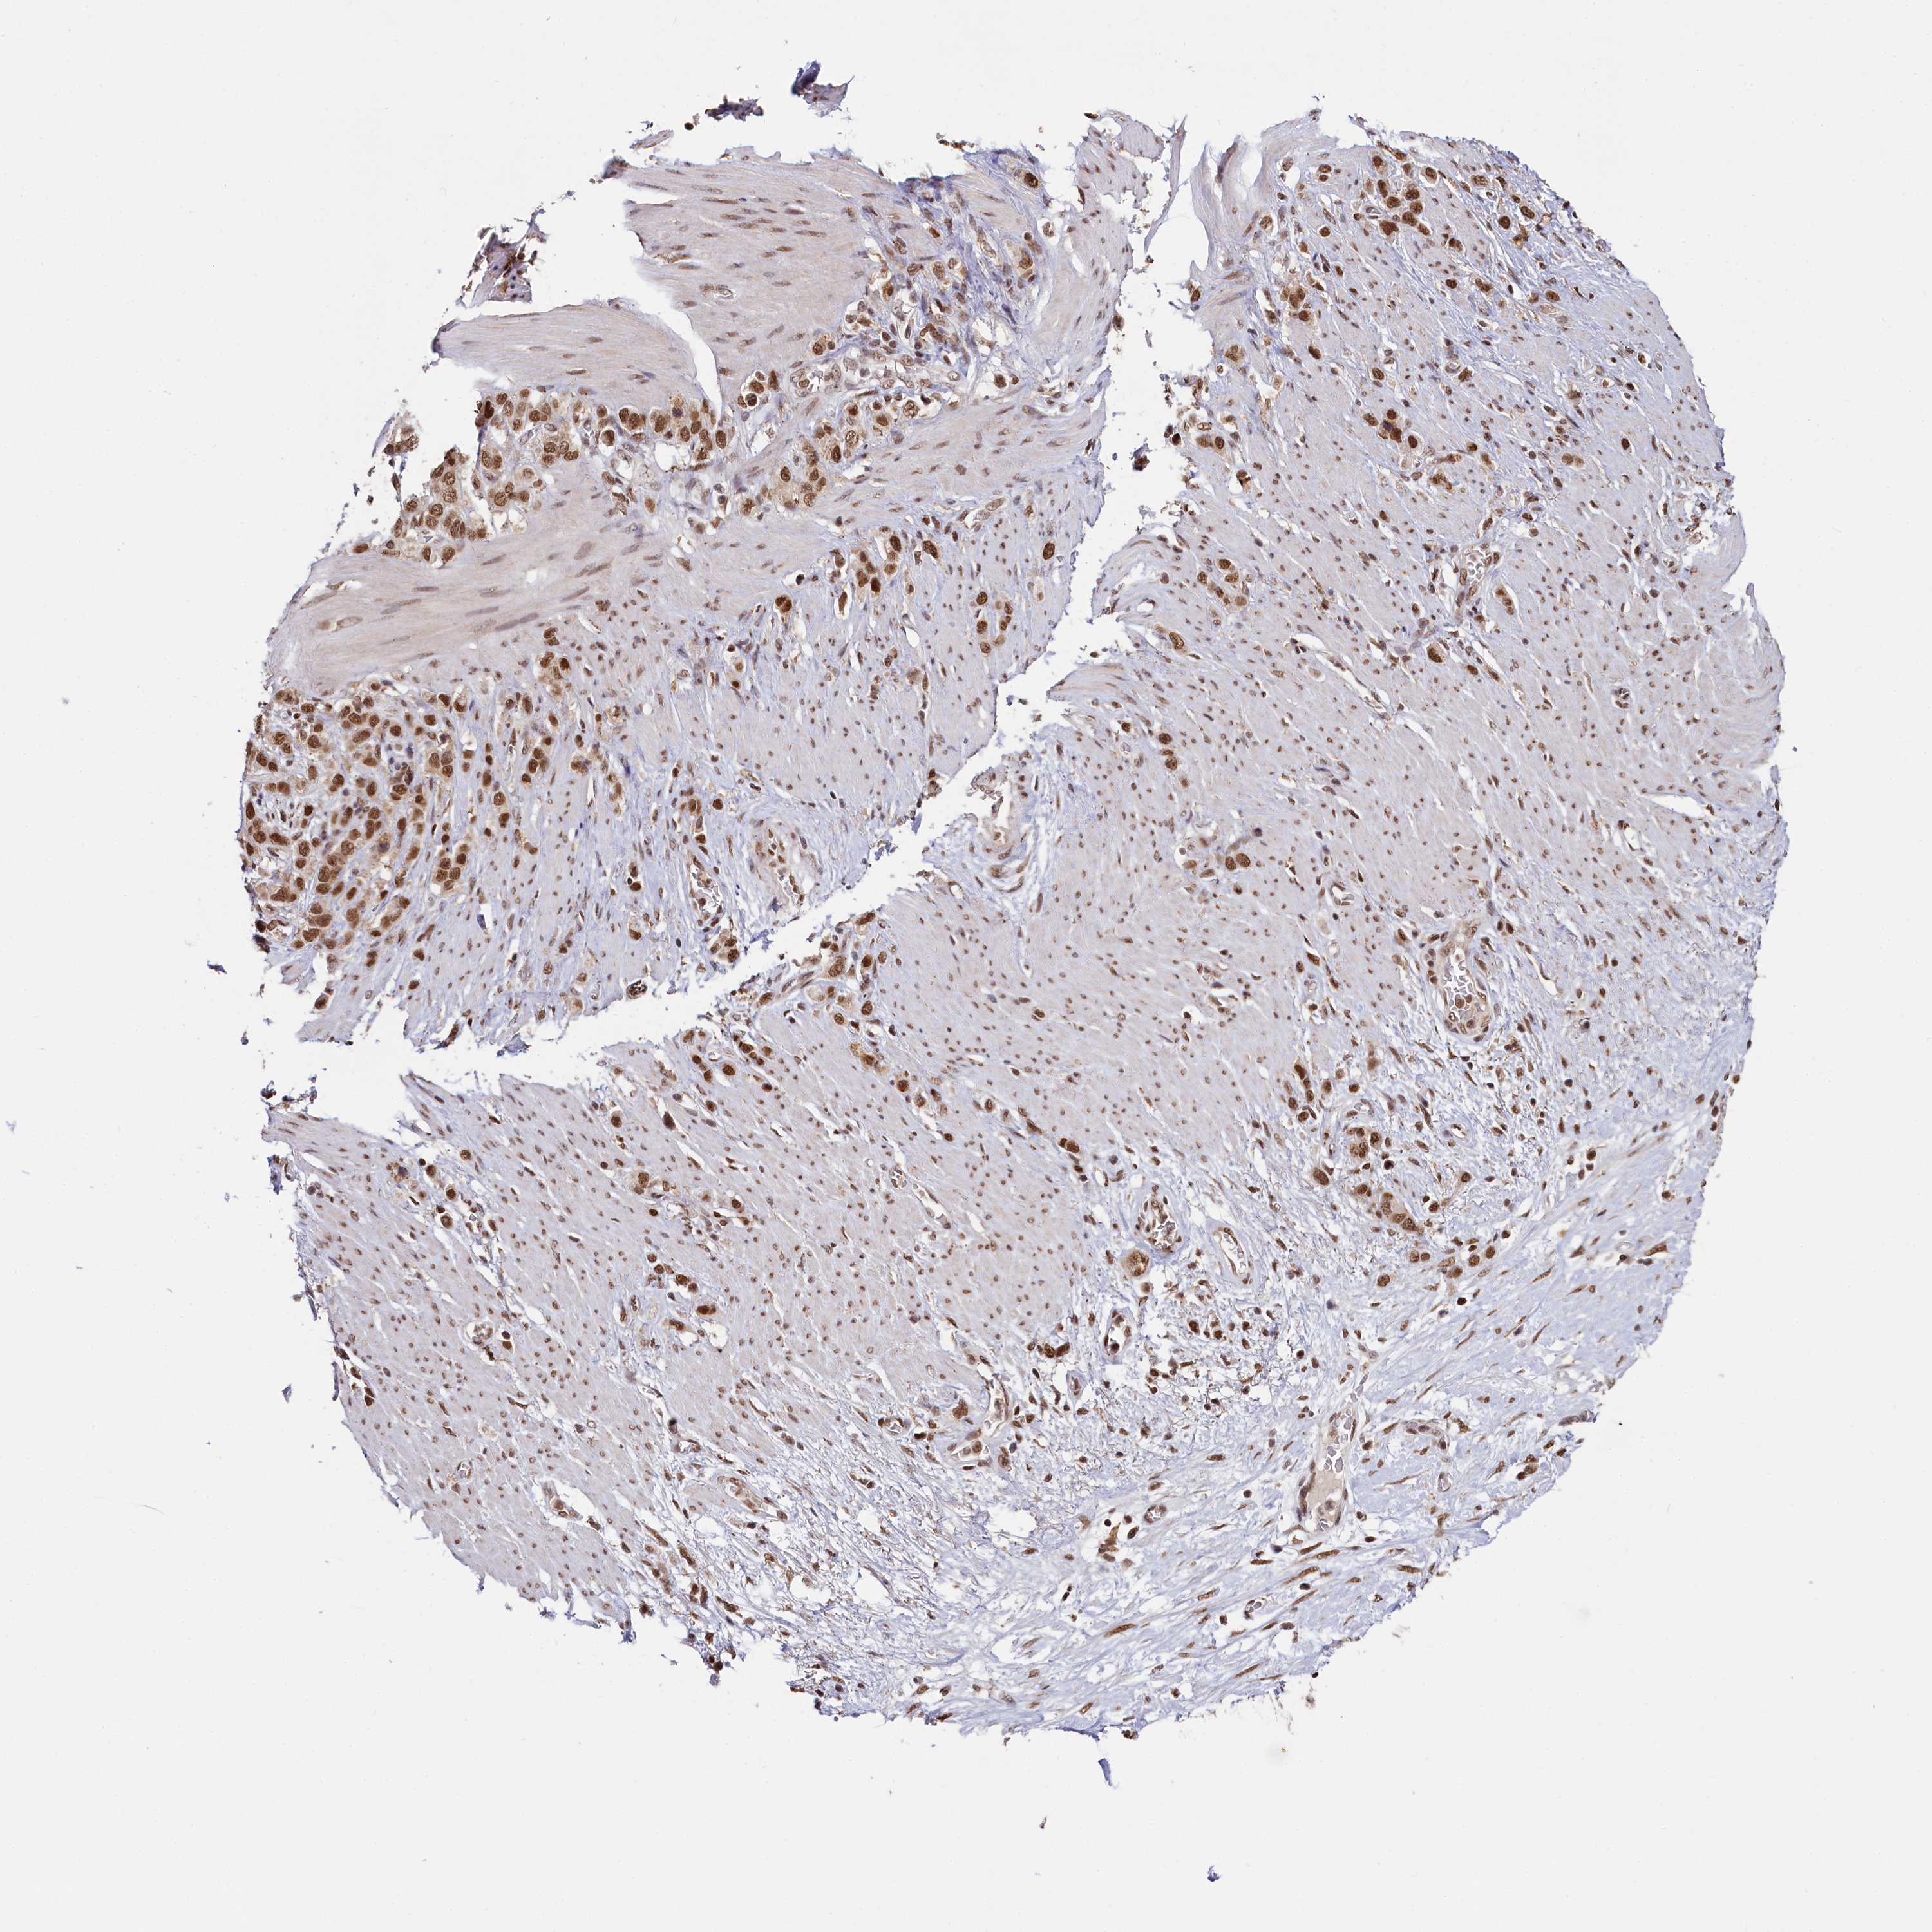

STOMACH CANCER - Protein expressioni

A mouse-over function shows sample information and annotation data. Click on an image to view it in a full screen mode. Samples can be filtered based on level of antibody staining by selecting one or several of the following categories: high, medium, low and not detected. The assay and annotation is described here.

Note that samples used for immunohistochemistry by the Human Protein Atlas do not correspond to samples in the TCGA dataset.

Antibody stainingi

Antibody staining in the annotated cell types in the current human tissue is reported as not detected, low, medium, or high, based on conventional immunohistochemistry profiling in selected tissues. This score is based on the combination of the staining intensity and fraction of stained cells.

Each image is clickable and will lead to virtual microscopy that enables deeper exploration of all samples and also displays staining intensity scores, fraction scores and subcellular localization as well as patient and tissue information for each sample.

Antibody HPA038902

Antibody HPA038903

Staining

High

Medium

Low

Not detected

Intensity

Strong

Moderate

Weak

Negative

Quantity

>75%

75%-25%

<25%

None

Location

Nuclear

Cytoplasmic/membranous

Cytoplasmic/membranous,nuclear

Adenocarcinoma, NOS

Adenocarcinoma, High grade